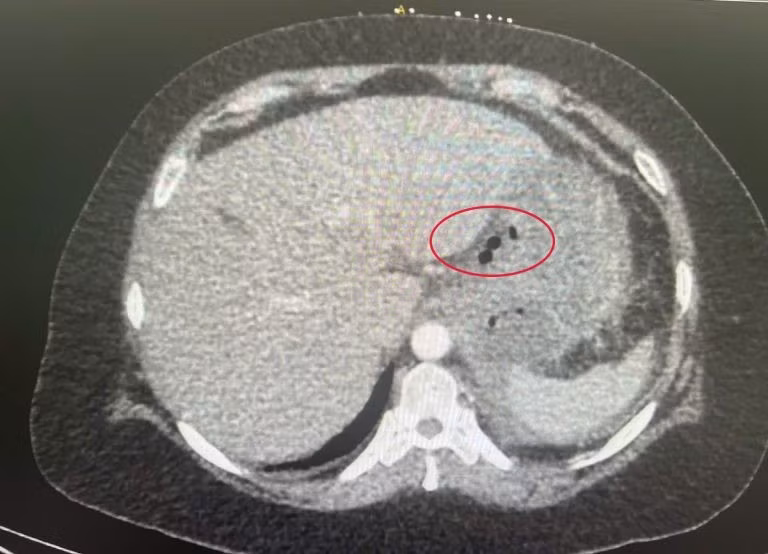

Hình ảnh cận lâm sàng cho thấy xương cá trong dạ dày - Ảnh BVCC